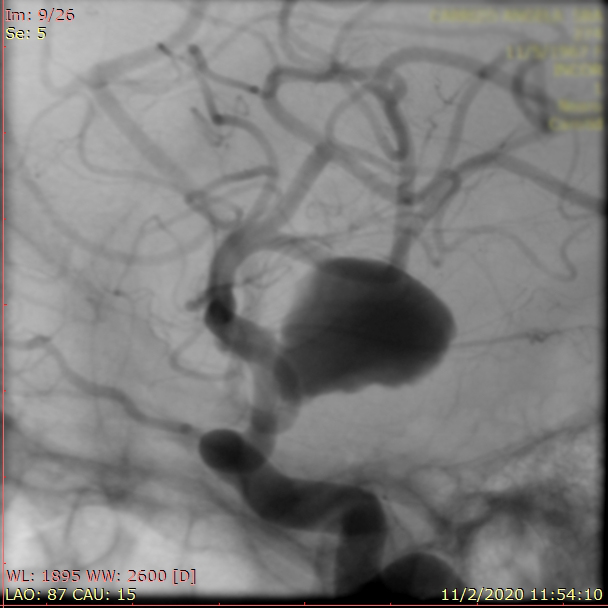

La paciente ingreso al Servicio de Hemodinamia el día martes 11 de febrero con un aneurisma cerebral gigante en la carótida izquierda y se le practicó una embolización; es decir una oclusión por dentro del mismo, donde se colocó un dispositivo denominado coils más un stent diversor de flujo. El procedimiento fue exitoso y contó con la colaboración de médicos neurointervencionistas del Instituto Oulton de la Ciudad de Córdoba.